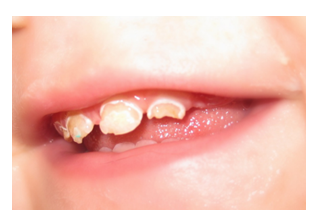

Prema spoljašnjem izgledu oštećenja gleđi nepravilnosti mogu da budu samo u obliku promene boje(bela, žućkasta) sto se naziva stručno HIPOMATURACIJA(bele mrlje-videti na kraju teksta), ili pravih defekata nepravilnog oblika što se naziva HIPOPLAZIJA.(slika 1.)

Razvojna oštećenja su posledica stvaranja manje kvalitetne gleđi ili potpunog nedostataka gleđi na pojedinim mestima. Ponekada, po nicanju zuba, takva gleđ je samo promenjenog izgleda(hipomaturacija), ali je slabije mehaničke otpornosti i usled pritisaka dolazi do njegnog pucanja i prelaska u defekt(hipoplaziju).